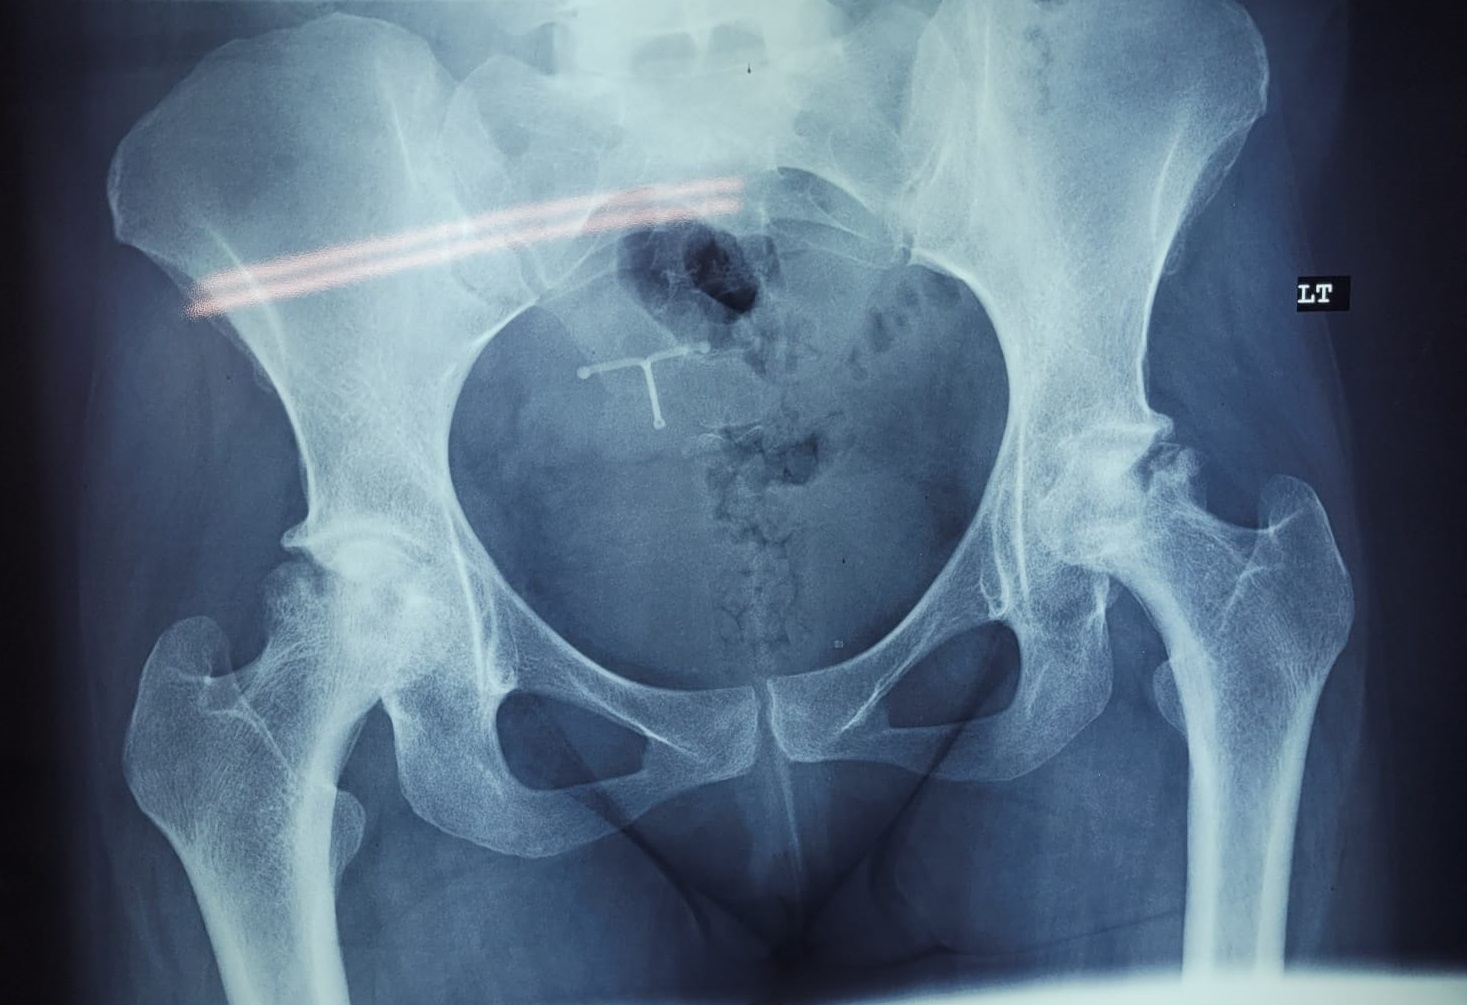

Patient 23

38 year old with avascular necrosis of the hip

Ceramic on poly articulation